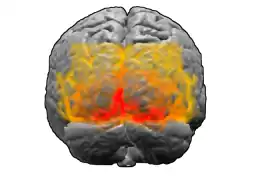

De visuele cortex,[1] visuele schors, optische schors,[2] cortex visualis of gezichtsschors[3][4][5] is het deel van de occipitale kwab (achterhoofdskwab) van de hersenen dat betrokken is bij de visuele waarneming.

De visuele schors van apen en mensen kan worden onderverdeeld in de area striata (Latijn: striata, "gestreept") en de area extrastriata (Latijn: extra, "buiten"). Het eerste gebied dankt zijn naam aan de opvallende streep van Gennari van merghoudende vezels, die zichtbaar is onder de microscoop. Aangezien de visuele informatie dit schorsveld als eerste van alle gebieden van de cortex cerebri bereikt, staat dit gebied ook bekend als de primaire visuele schors of area V1 (V=visualis/visueel). In de indeling van de cortex cerebri van Korbinian Brodmann, is dit area 17. Het tweede gebied dankt zijn naam aan het feit dat het buiten (extra) de area striata ligt en bevat area 18 en area 19 van Brodmann.

De area striata ligt aan de achterkant van de grote hersenen aan de mediale zijde in de fissura calcarina[6]. De fissura calcarina is een hersengroeve die van de polus occipitalis (achterhoofdspool) richting het achterste gedeelte van de hersenbalk (splenium corporis callosi) loopt en daar samenvloeit met de diagonaal verlopende sulcus parietoocipitalis[6]. Tot aan deze vereniging (van achter naar voren bezien) spreekt men over de truncus fissurae calcarinae[6]. De fissura calcarina loopt beperkt door over de polus occipitalis over de buitenzijde van de grote hersenen (facies convexa). De area striata ligt daarom voor het grootste gedeelte aan de mediale zijde van de grote hersenen en maar voor een klein gedeelte op de buitenkant[6].

De area striata loopt voor een deel door in de bovenliggende cuneus (wig)[6] en de onderliggende gyrus lingualis (tongwinding)[6], die beide onderdeel vormen van de occipitale kwab.

De area extrastriata is het gebied van de gezichtsschors dat buiten de area striata ligt. Het overige deel van de occipitale kwab wordt ingenomen door de area extrastriata. Naast het overgebleven deel van de gyrus lingualis loopt de area striata over de meer zijdelings verlopende gyrus fusiformis. In tegenstelling tot de area striata, is de area extrastriata duidelijk zichtbaar aan de buitenkant van de grote hersenen op de occipitale kwab.